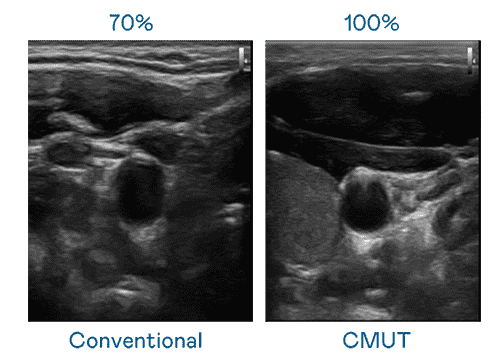

CMUT 技术是一种用电容式微机电元件来产生超音波讯号的技术。。。。与传统 PZT 压电式技术相比,,,,CMUT 频宽增加 30%,,,,更宽频的超音波讯号让影像解析度大幅提升,,,是实现高影像品质医疗超音波扫描、、、促进精准医疗发展的关键技术。。

大频宽带来超清晰影像

超音波影像的解析度高低,,,,首先取决于探头能发出的讯号频宽。。。尊龙集团 CMUT 可提供高清晰的超音波讯号,,提供高频宽、、、、高灵敏度、、、、影像纹理细节更高的超音波影像,,,,协助医护人员缩短影像判读时间及利用精准的医疗影像进行诊断。。。